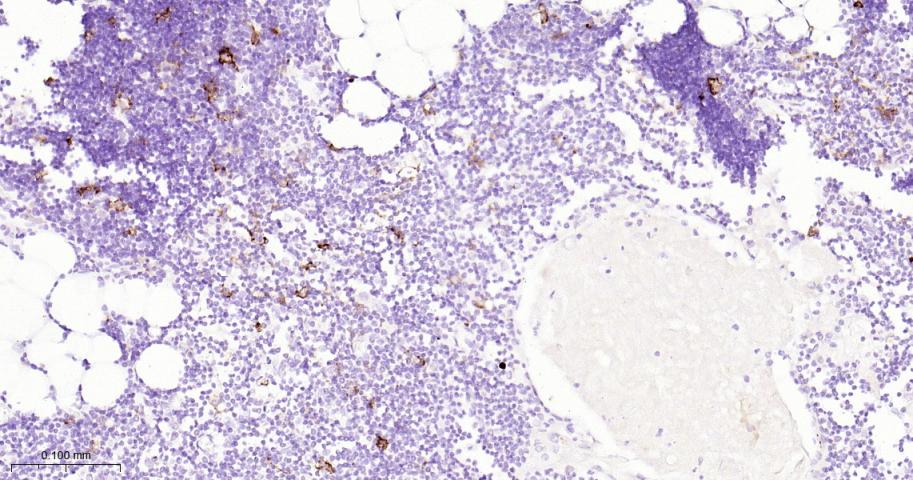

Paraformaldehyde-fixed, paraffin embedded Human Spleen; Antigen retrieval by boiling in sodium citrate buffer (pH6.0) for 15 min; Antibody incubation with CD16a Monoclonal Antibody, Unconjugated(bsm-60782R) at 1:200 overnight at 4°C, followed by conjugation to the bs-0295G-HRP and DAB (C-0010) staining.